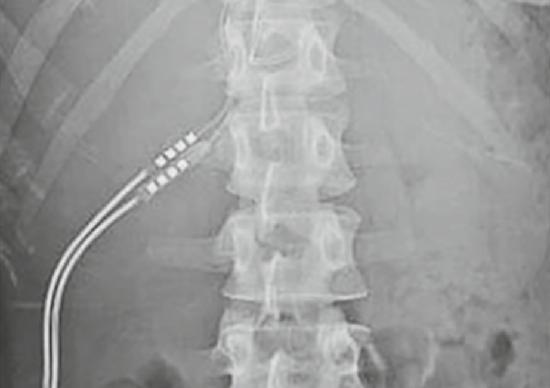

Aanslepende rugpijn gekalmeerd

Een degelijke toepassing van invasieve neuromodulatie is de behandeling van aanslepende rugpijn. ‘Het gaat dan vooral om patiënten die zonder succes een rugoperatie hebben ondergaan en kampen met rugpijn die uitstraalt naar het been, waarbij die laatste pijn primeert. Bij die patiënten wordt een elektrode aangebracht op het vlies rondom het ruggenmerg’, zegt UZA-neurochirurg dr. Niels Kamerling. De zenuwbaan in kwestie wordt gestimuleerd, wat een pijnstillend effect heeft. Via een afstandsbediening kunnen patiënten de intensiteit van de stimulatie aanpassen.

Situeert de pijn zich hoofdzakelijk in het been en is er maar één zenuw bij betrokken, dan gebeurt

de behandeling onder lokale verdoving in het pijncentrum, met behulp van een holle naald. Bij een meer uitgebreide problematiek is een klassieke operatie onder narcose nodig, uitgevoerd door de neurochirurg. Patiënten komen maar in aanmerking als de andere behandelingen zijn uitgeput. Ze ondergaan eerst een voorlopige ingreep, waarbij de elektrode wordt geplaatst maar de pacemaker nog niet wordt ingeplant. ‘Na die ingreep wachten we minstens vier weken’, zegt pijnarts dr. Liesbeth Teugels. ‘We geven groen licht als er aan drie voorwaarden is voldaan: de patiënt heeft minder pijn, hij gebruikt minder pijnmedicatie en hij kan opnieuw beter functioneren.’ Hoewel het resultaat bij sommige patiënten na verloop van maanden afneemt, ondervindt de meerderheid blijvende verbetering. Neuromodulatie kan ook worden

Via een afstandsbediening kunnen rugpatiënten de intensiteit van de stimulatie aanpassen.

Bij sommige patiënten met aanslepende rugpijn wordt een zenuwbaan gestimuleerd via een elektrode op het vlies rondom het ruggenmerg. Daardoor vermindert de pijn.